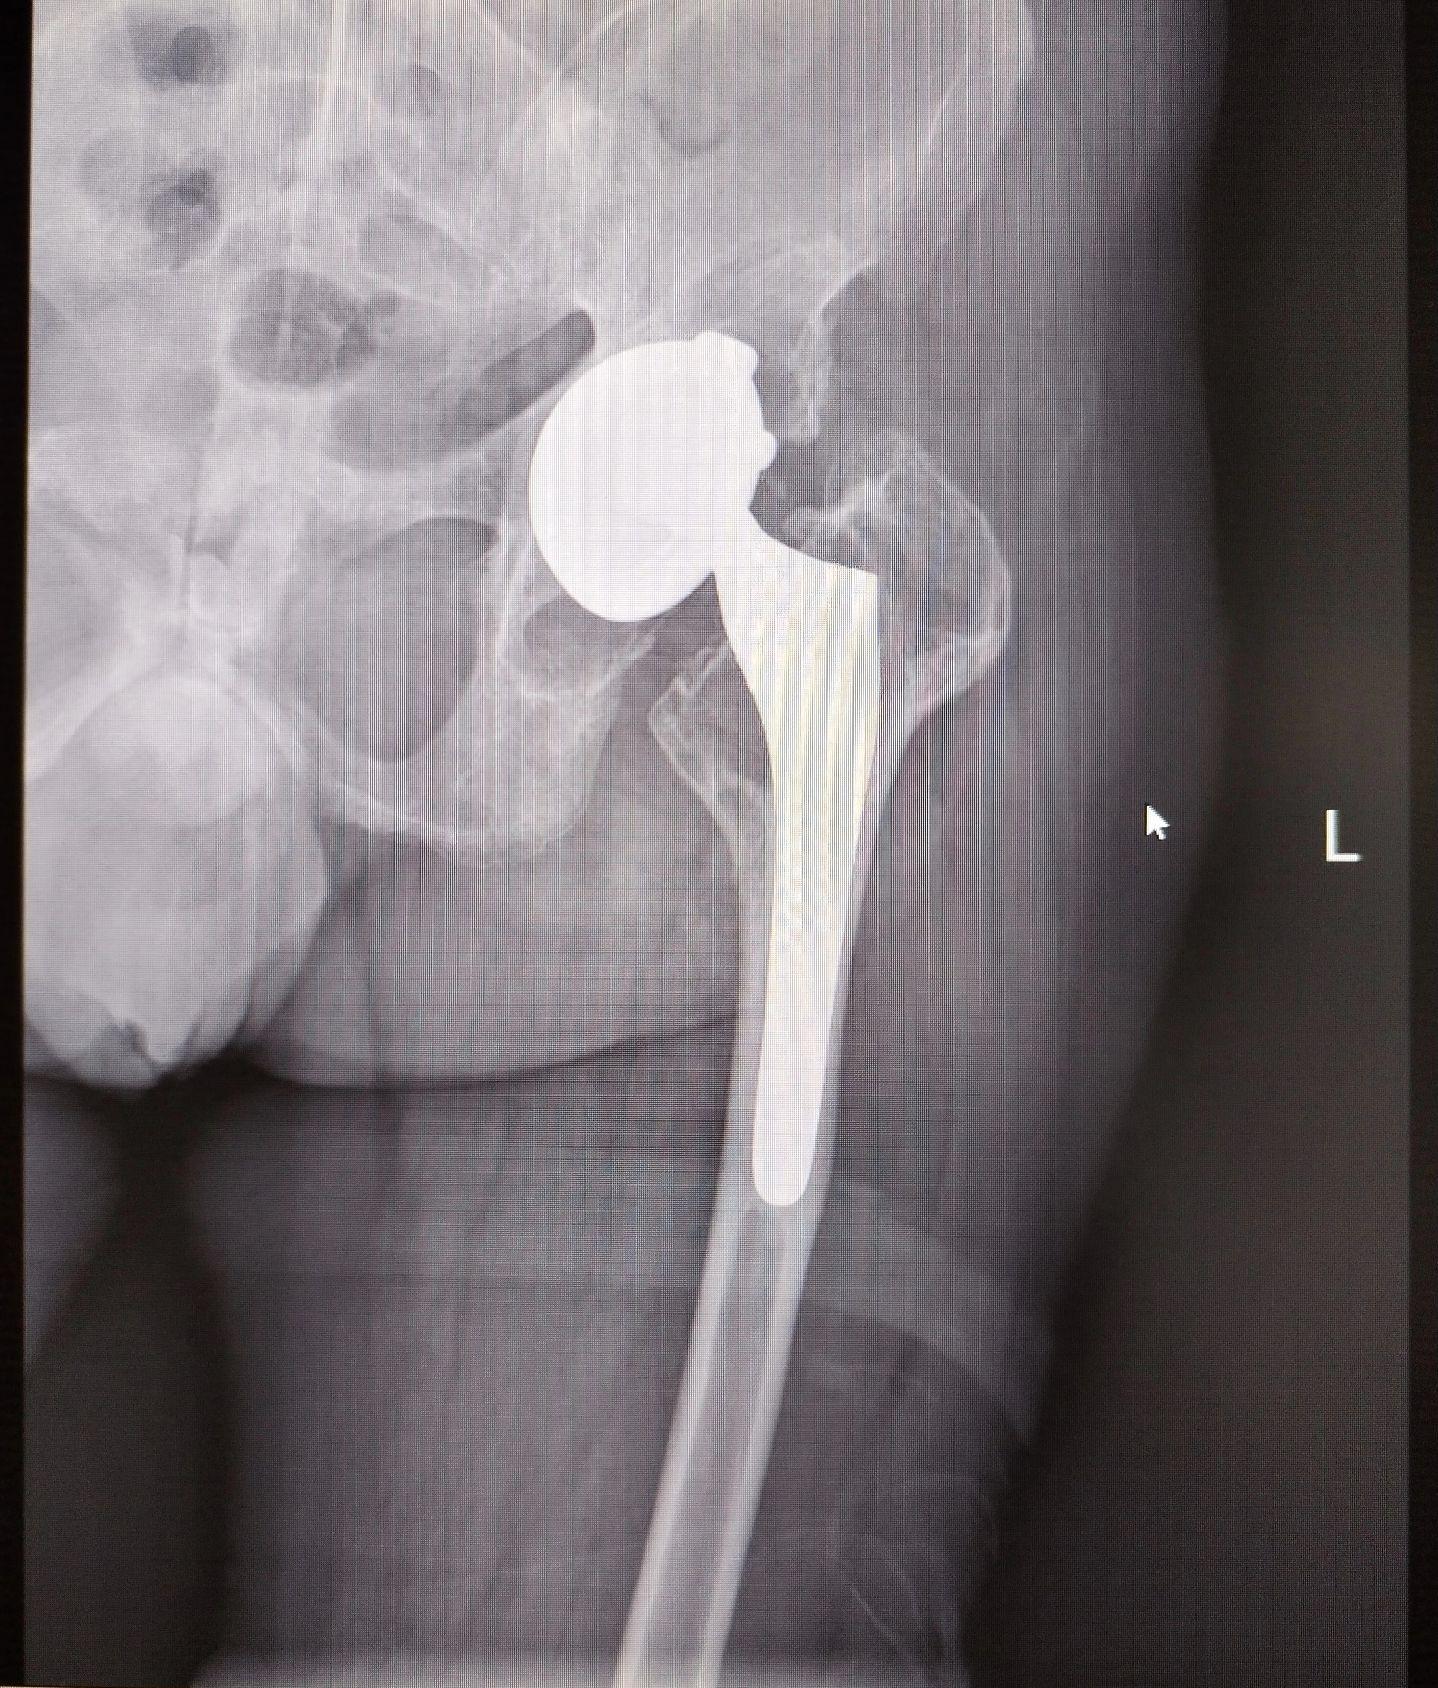

髋关节翻修术。髋关节置换术后假体磨损松动,双侧分次翻修。